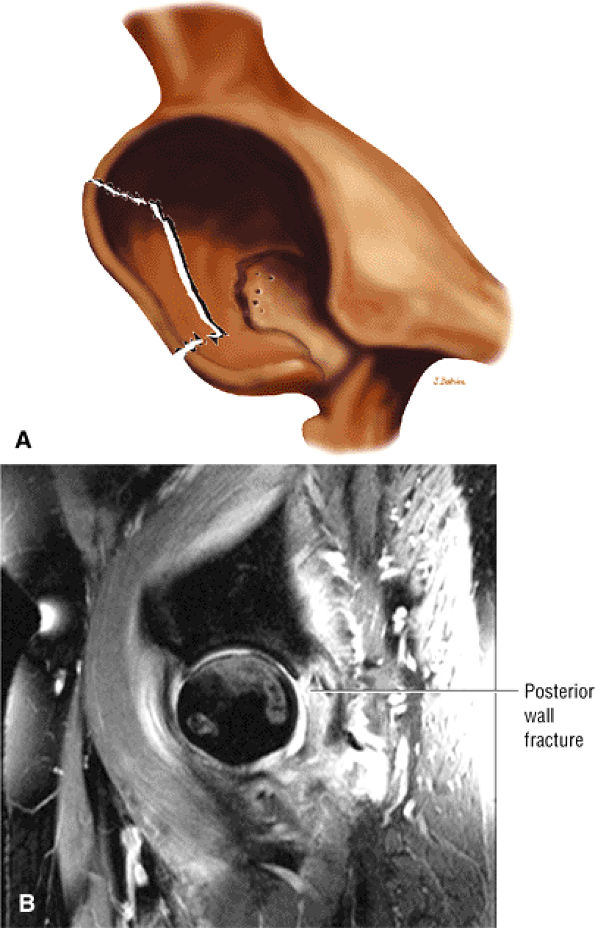

A decreased femoral head-neck offset

-

A dysplastic femoral bump at or adjacent to the lateral physeal scar femoral head-neck junction (Fig. 3.185)